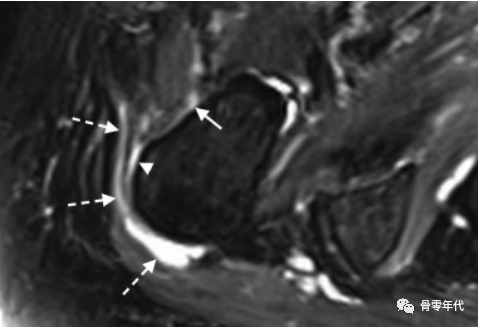

71岁女性臀小肌腱部分厚度撕裂(a和b中的箭头):(a)脂肪饱和冠状质子密度加权图像和(b)轴位T2加权脂肪饱和图像,伴有明显增厚和相关的小粗隆滑囊炎(b,虚线箭头)。(c)臀小肌腱在矢状位T1加权像上信号强度增加(星号)反映潜在的肌腱病变。